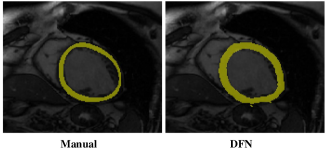

Refer to caption

(a) Epicardium segmentation results at ED frame.

(b) Endocardium segmentation results at ED frame.

Fig. 8: Visual comparison of segmentation results using different methods on LV-09 dataset. Epicardium slices in (a) and endocardium slices in (b) are from one subject at testing set. Please refer to the electronic version for better comparison. Top to bottom: the basal, mid-ventricular and apical slices from the same subject. Left to right: manual labeling, majority voting (MV), patch-based method (PB), SVM segmentation with augmented features (SVMAF), DFN_NMI using LF registration, DFN_NMI, DFN using LF registration, and DFN. The small white text in each sub-image is the corresponding 2D Dice metric value.

Our DFN and DFN_NMI based on LF registration achieve lower values of “Good” percentage in all comparisons, due to the inaccurate registration results without using landmarks on this dataset. This indicates that our method, as a multi-atlas segmentation method, relies on a relatively good registration method, and breaks down on LV-09 dataset when LF registration does not work well. Figure 7 compares the segmentation accuracies in the box-plot, and Figure 8 shows the epicardium and endocardium segmentation results using different methods for the basal, mid-ventricular and apical slices from one subject in testing set.